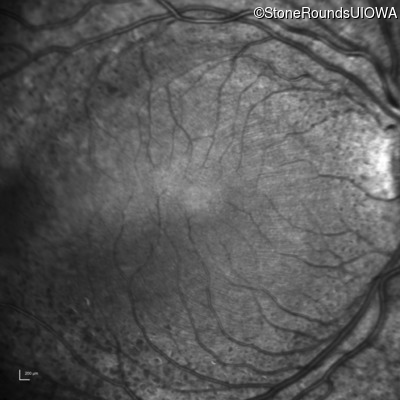

Infrared Fundus Photograph - Right - 20/50

Exemplar